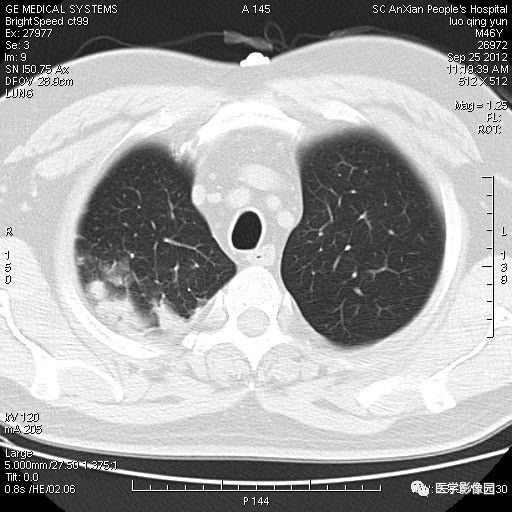

影像学表现:右上肺见不规则团块状高密度阴影,略有分叶级毛刺,边缘模糊,邻近胸膜增厚,增强扫描呈轻中度强化。

诊断结果:右上肺炎性假瘤

本病影像学表现无绝对特征性。单发多见,多位于肺表浅部位,多呈圆形或椭圆形,直径多在2-5cm或更大;多有假包膜,边缘多清晰光整,有时也毛糙,并可有分叶或毛刺;邻近胸膜局限性增厚、牵拉,病灶边缘呈桃尖样突起即桃尖征(尖端指向胸膜);增强扫描多呈中度均匀强化,持续时间较长。亦可显著强化。